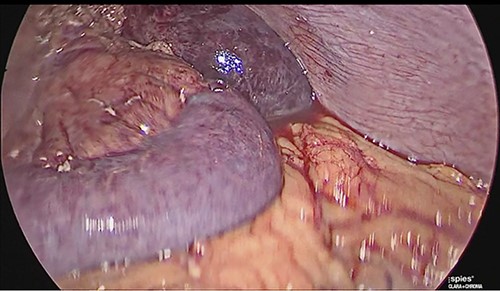

The patient was reoperated by laparoscopy, finding segmental thrombosis from 200 cm to 50 cm of the Treitz ligament, with edema and interloop free fluid without perforation (Figs 3 and 4). Lateral resection and entero–entero anastomosis were performed with manual stapler, subtracting 440 cm of intestine with adequate coloration. Later he was admitted to the Intensive Care Unit, treated with low molecular weight heparin at a full anticoagulation dose, maintaining an INR of 2 and a partial thromboplastin time of 80 s. He presented adequate evolution starting a liquid diet on the fourth postoperative day, new laboratories reported hemoglobin of 11 g/dl, 12 700 leukocytes/mm3, platelets 225 000/mcL, INR of 2. He was discharged on the fifth day with rivaroxaban treatment for 6 months.

Laparoscopic view of intestinal thrombosis 200 cm at the level of the proximal jejunum, 50 cm from the ligament of Treitz.

Laparoscopic view of intestinal thrombosis and free fluid in the cavity.